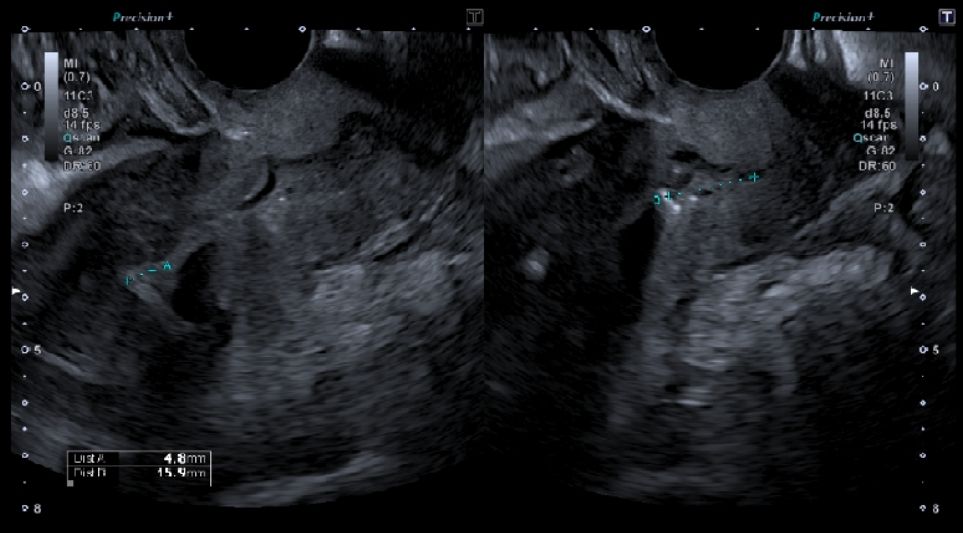

- Via endocavitária (endovaginal): a sonda é introduzida na vagina, permitindo uma visualização mais próxima e detalhada do útero e dos ovários. Esta sonda é introduzida com uma proteção descartável e uma pequena quantidade de gel lubrificante na sua extremidade, para facilitar a introdução e melhorar a transmissão da imagem. Saiba mais em Ecografia Pélvica / Ginecológica por via endocavitária.

Durante o exame, a paciente permanece deitada numa maca, numa sala pouco iluminada para facilitar a leitura das imagens. As imagens em movimento são observadas em tempo real num ecrã e interpretadas pelo médico especialista. O procedimento dura habitualmente entre 15 e 30 minutos.

A ecografia ginecológica é um exame fundamental para a avaliação da saúde reprodutiva e ginecológica da mulher. Permite identificar alterações como miomas uterinos e pólipos endometriais, quistos nos ovários (funcionais, hemorrágicos ou patológicos) e variações do endométrio, seja por espessamento ou atrofia. O exame ajuda ainda a detetar malformações uterinas, anomalias congénitas, sinais de endometriose ou inflamações pélvicas. As trompas de Falópio podem igualmente ser avaliadas, nomeadamente no caso de dilatações ou obstruções, e, através do Ecodoppler, é possível estudar o fluxo sanguíneo pélvico. Para além do diagnóstico, esta ecografia tem um papel importante no acompanhamento de tratamentos de fertilidade, na monitorização da resposta a tratamentos hormonais e no seguimento após cirurgia.